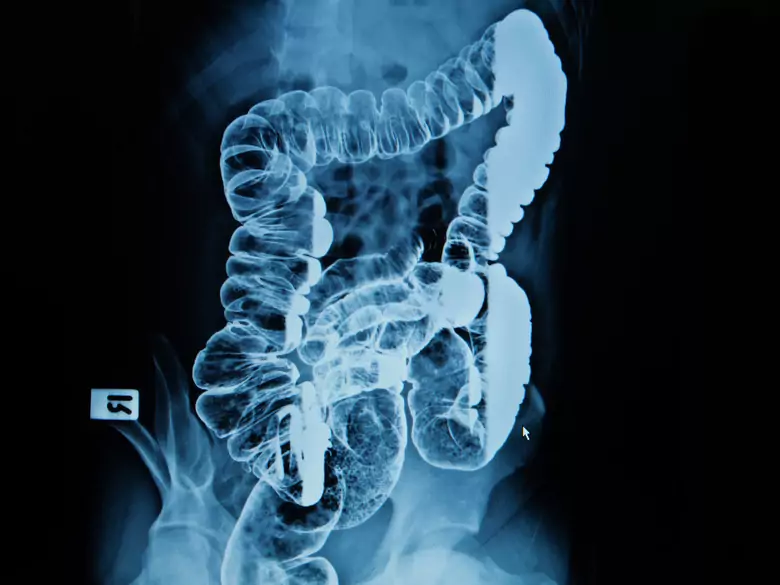

PantherMedia

Darmuntersuchung